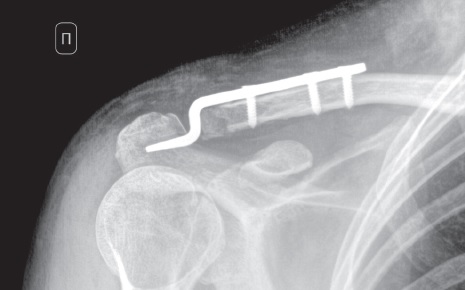

Идентичное по высоте смещение центрального отломка ключицы с клювовидным отростком лопатки позволяло косвенно судить об интактных ключично-клювовидных связках. На наш взгляд, предпочтительным имплантатом для решения данной задачи была и остается крючковидная пластина (hook-plate). В первые сутки госпитализации пациентке была выполнена операция: открытая репозиция отломков, фиксация крючковидной пластиной с винтами. Во время выполнения операции на основании рентгеноконтроля было принято окончательное решение не фиксировать дополнительно клювовидный отросток лопатки (рис. 2).

Рис. 2. Интраоперационная рентгенограмма правого акромиально-ключичного сустава в переднезадней проекции: состояние после открытой ручной репозиции отломков, фиксации крючковидной пластиной акромиального конца правой ключицы. Смещение отломков устранено

Fig. 2. Intraoperative X-ray of the right AC joint in AP view after open manual reduction and fixation of the right distal clavicle with a hook plate. Displacement of fragments is eliminated

После устранения смещения отломков ключицы и воссоздания анатомических взаимоотношений в акромиально-ключичном суставе вследствие восстановления баланса тяги сухожилий мышц, фиксирующихся к клювовидному отростку, произошла его анатомическая репозиция. В связи с этим было принято решение дополнительно не фиксировать клювовидный отросток лопатки.